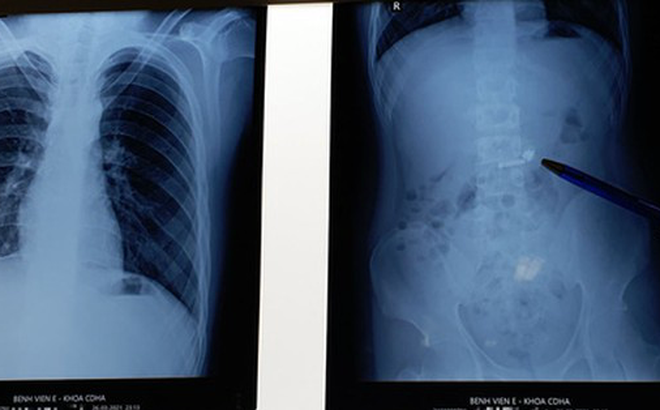

Kết quả chụp X-quang tại bệnh viện cho thấy trong ổ bụng bệnh nhân có hình tai nghe điện thoại không dây. Đáng nói, bệnh nhi là trẻ tự kỷ nên việc điều trị không dễ dàng. Bệnh nhân không hợp tác với các thầy thuốc trong việc lấy máu làm xét nghiệm, chiếu chụp và gây mê... Phải gần 4 tiếng sau vào viện, bác sĩ mới tiến hành nội soi để gắp dị vật cho bệnh nhân.

Chiếc tai nghe không dây nằm trong ổ bụng thiếu niên ở Hà Nội - Ảnh: Bệnh viện cung cấp

Bệnh nhi may mắn khi nuốt phải dị vật là hình dạng tròn, trơn bóng nên đã trôi xuống dạ dày mà không bị mắc lại ở vị trí thực quản hay đường thở, tránh được nhiều biến chứng nguy hiểm.